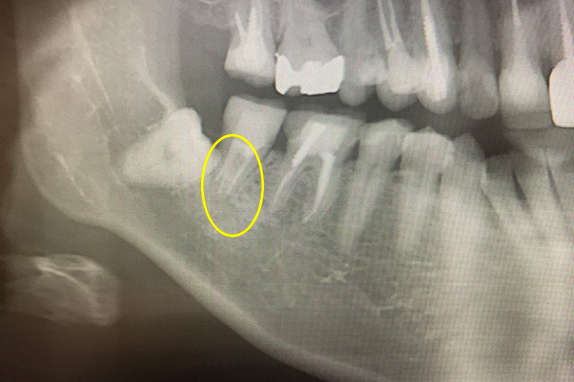

CASE 07 マイクロエンド(精密根管治療)+歯根周囲掻爬(歯周外科)

-

- 主訴

- 歯ぐきがよく腫れる(10代女性)

-

- 回数期間

- 7回 約1年半

-

- 治療法

- マイクロエンド(精密根管治療)、歯根周囲掻爬(歯周外科)

-

- 治療費用

- 約35万円(税抜)

歯ぐきがよく腫れる主訴で来院。レントゲン写真の術前を見ると大きな影が確認できます。この部分に嚢胞(のうほう)がある状態です。マイクロエンドと歯根周囲掻爬(歯周外科)をすることで改善したケースです。

<リスク・副作用>

治療後は痛み、腫れ、痺れなどの副作用が生じる場合があります。症状が再発する可能性があります。